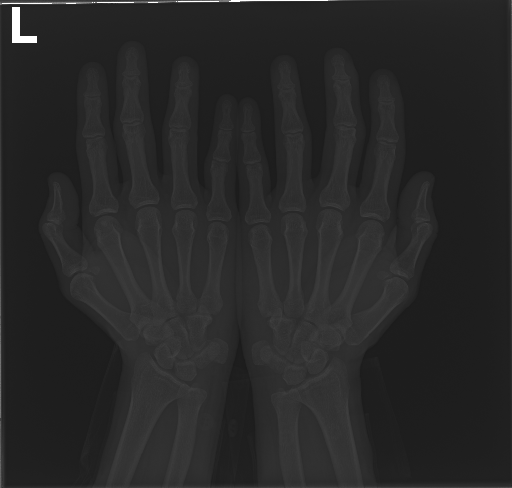

In this work, we focus on a subset of the MURA dataset [17] containing only hand images. In total, we have 5,543 images of 2,018 studies of 1,945 patients. Each study is labeled as negative or positive, where positive means that there was an anomaly diagnosed in this study. There are 521 positive studies, with a total of 1,484 images. Figure 1 shows some examples from the dataset. In summary, our contributions are as follows: